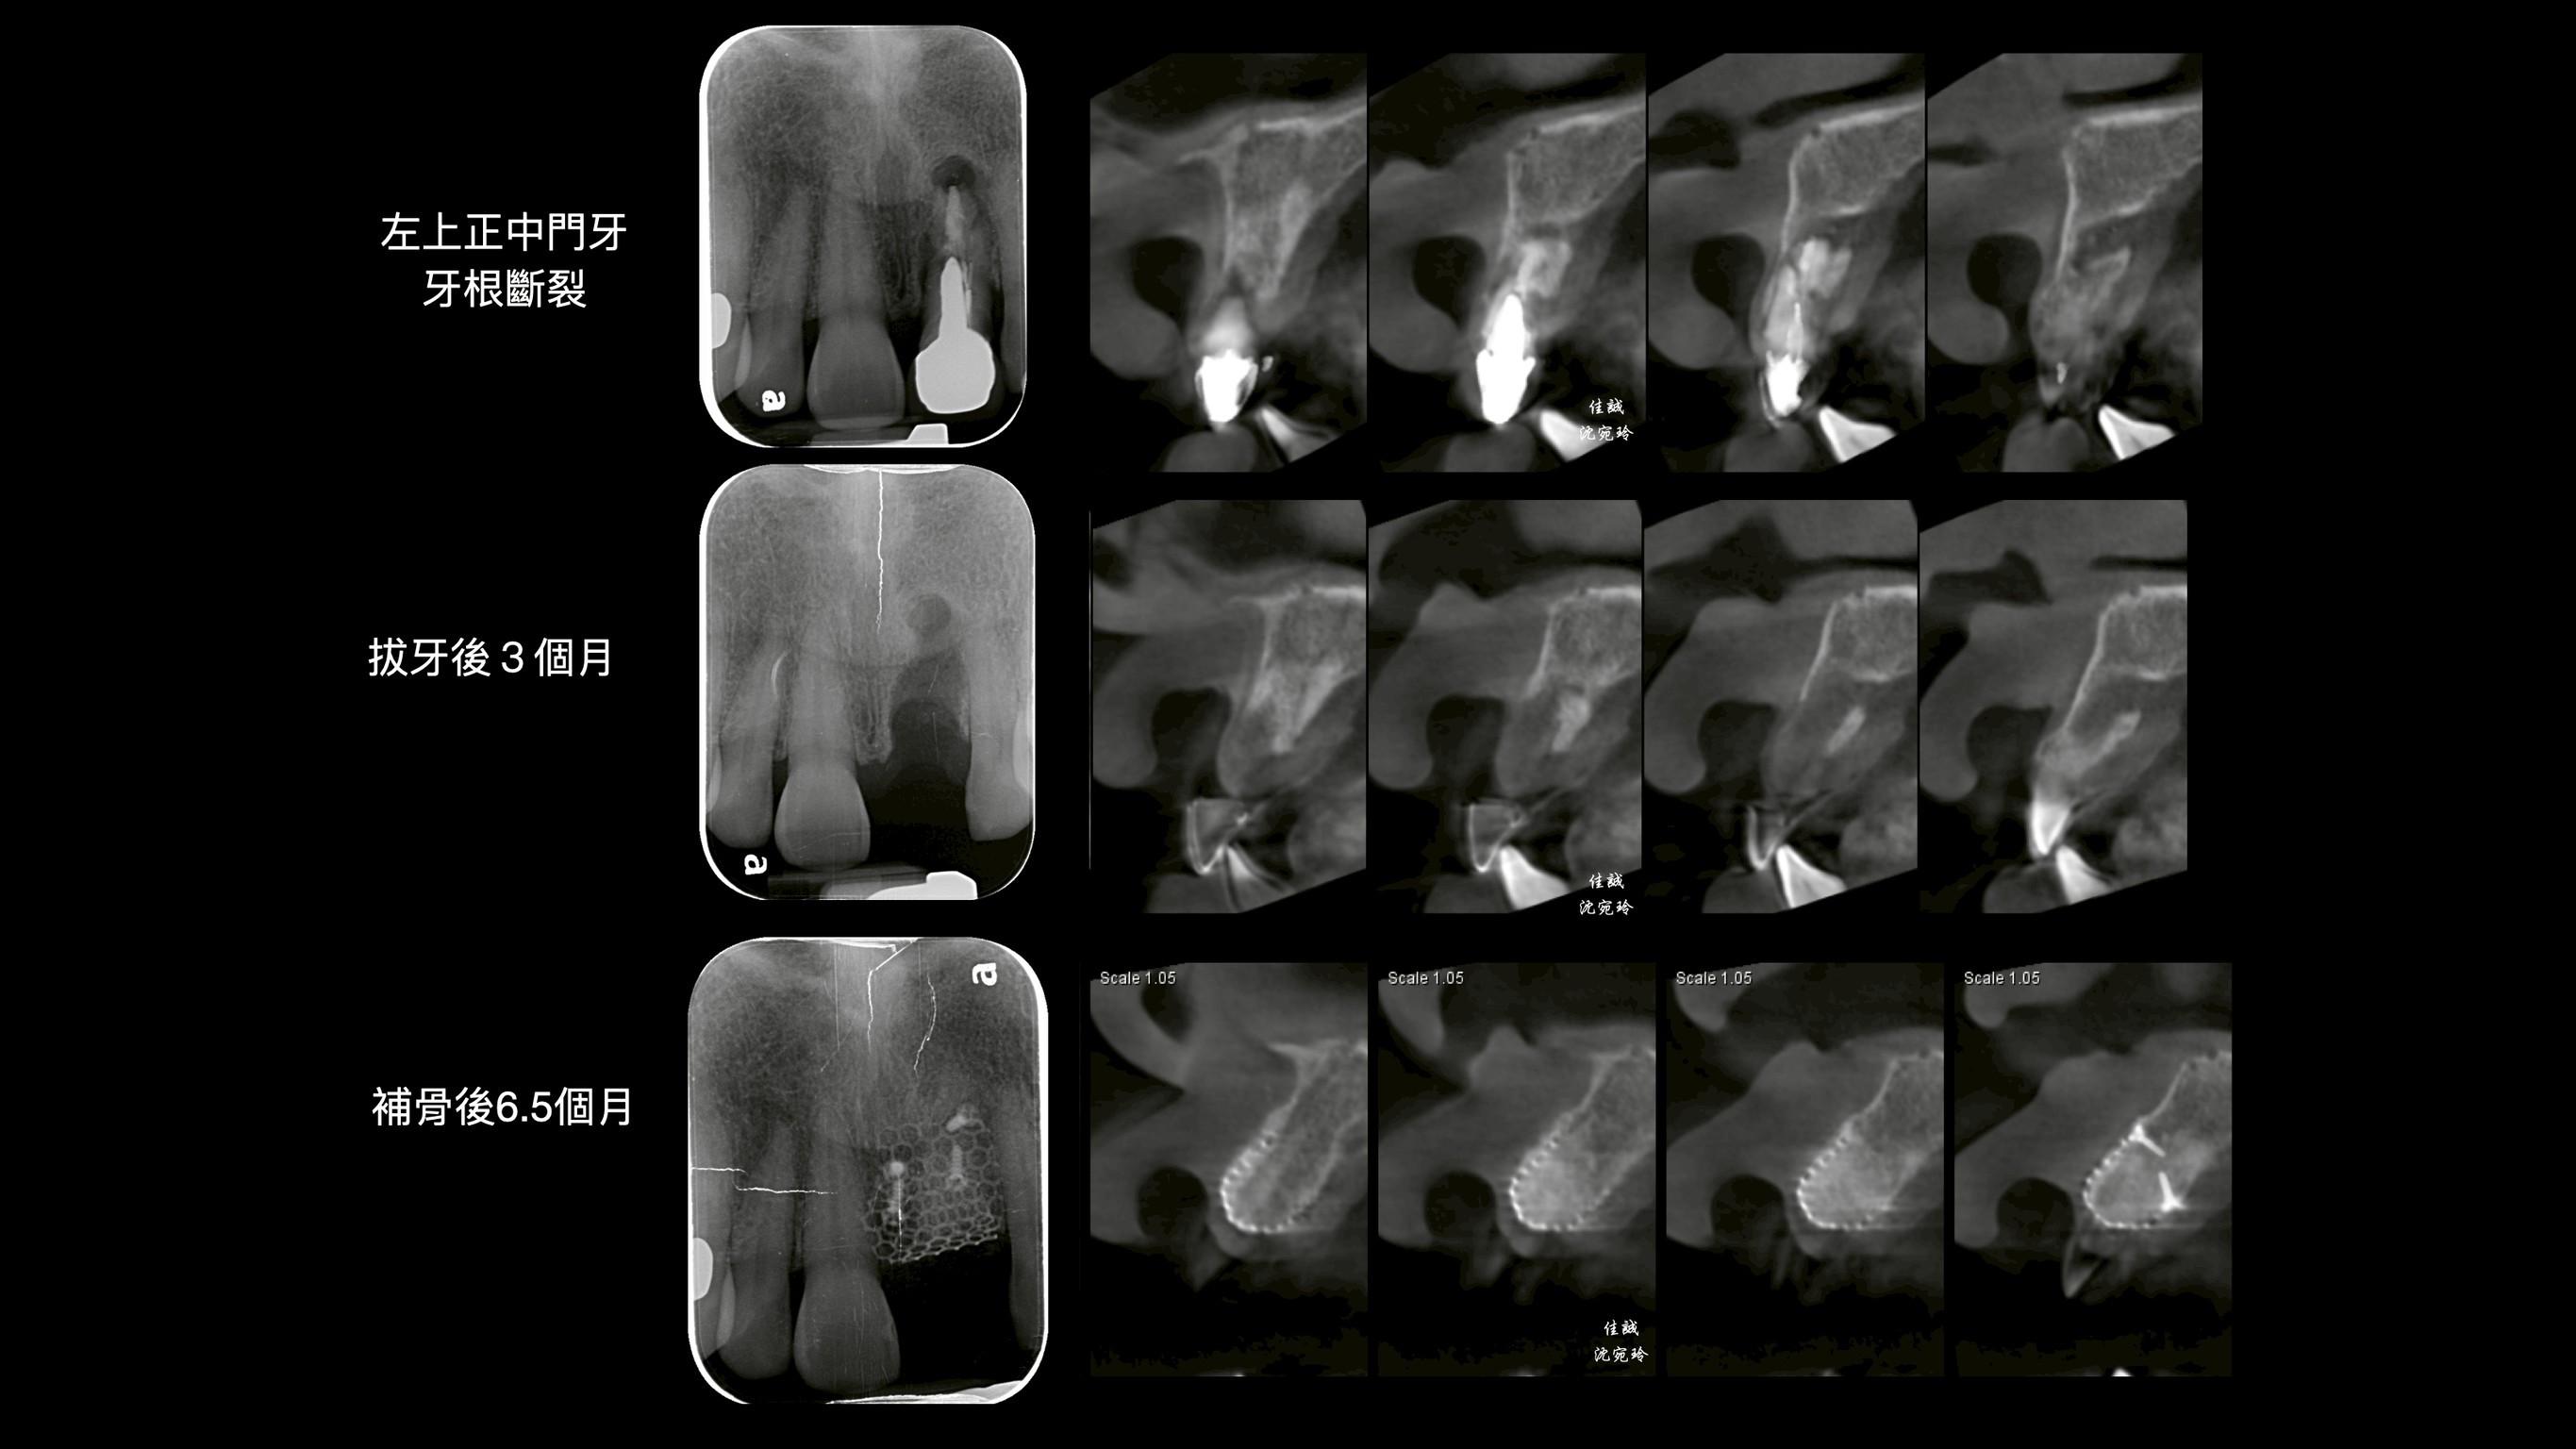

C小姐經其他醫師轉診,因上顎門牙牙根斷裂,感染而造成膿腫,在頰側、顎側、垂直高度皆有嚴重骨缺損。因此在補骨手術中,醫師選擇使用高難度的鈦網合併適度皮瓣減張,可以有效率的達到接近理想的成果。

其中,不論從診斷、補骨手術前及植牙的手術導板規劃階段,我們都會先把植體和其假牙相對位置找出來,來制定接下來的治療計劃。